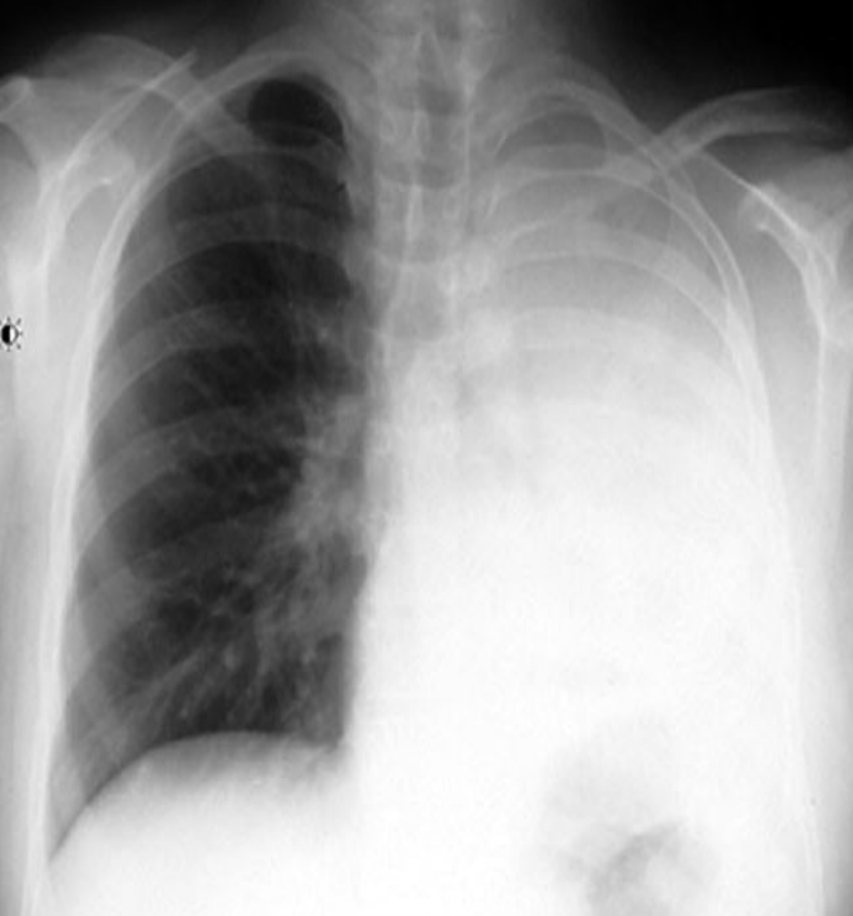

• Pleural effusion

• solid whiteness on right lung

• presence of meniscal line (looks like a U)